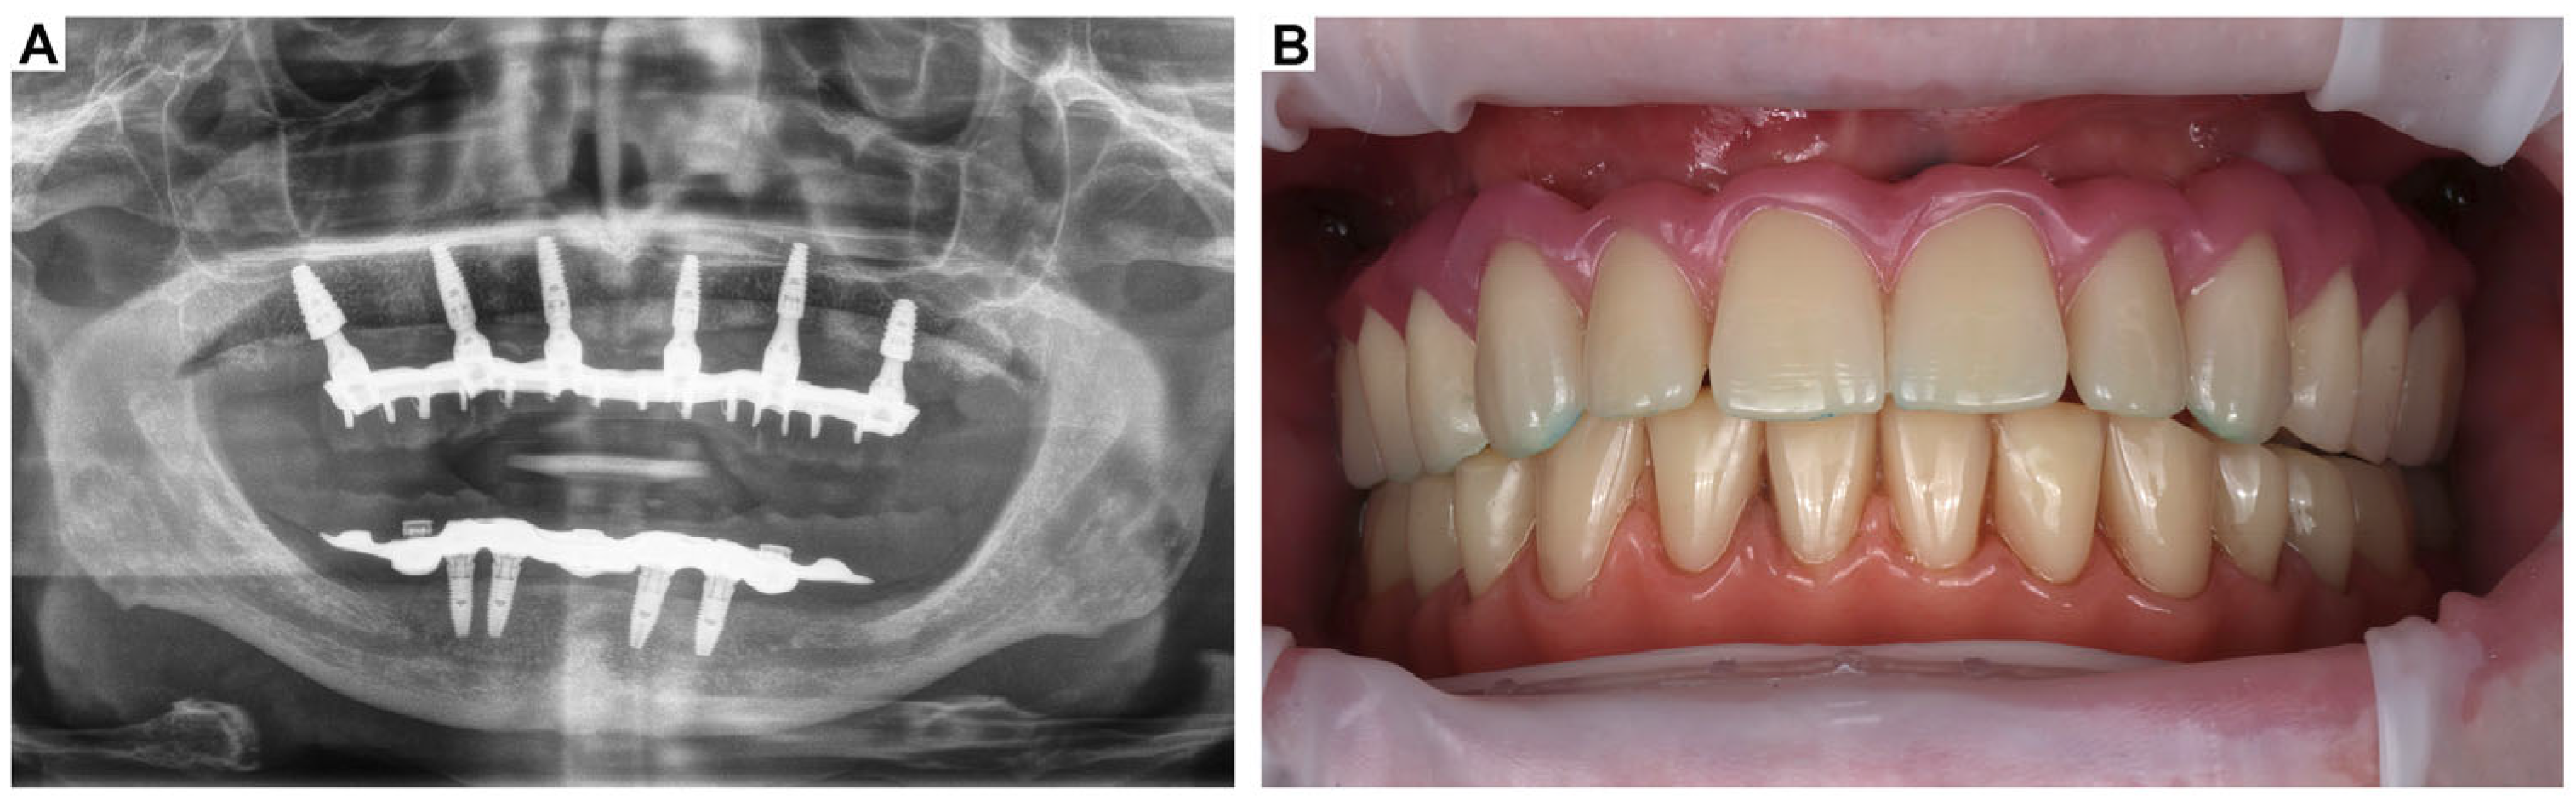

3. Clinical Cases Presentation of Advanced Implant Surgeries

3.2. Case Report-2